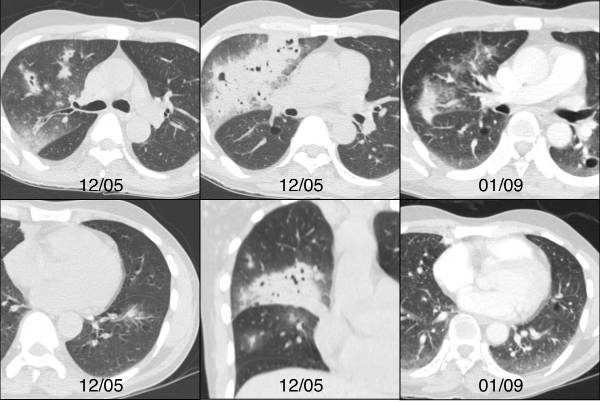

图3 骨髓移植患者双侧肺结节和实变,伴GGO。右图显示治疗后吸收良好。血管侵袭性曲霉病

外周实变代表存在继发于曲霉侵袭导致的远端肺血管堵塞的梗死区。

血管侵袭性曲霉病几乎全部见于免疫功能低下的患者,如严重中性粒细胞减少症患者、化疗中的肿瘤患者、异基因骨髓移植患者。